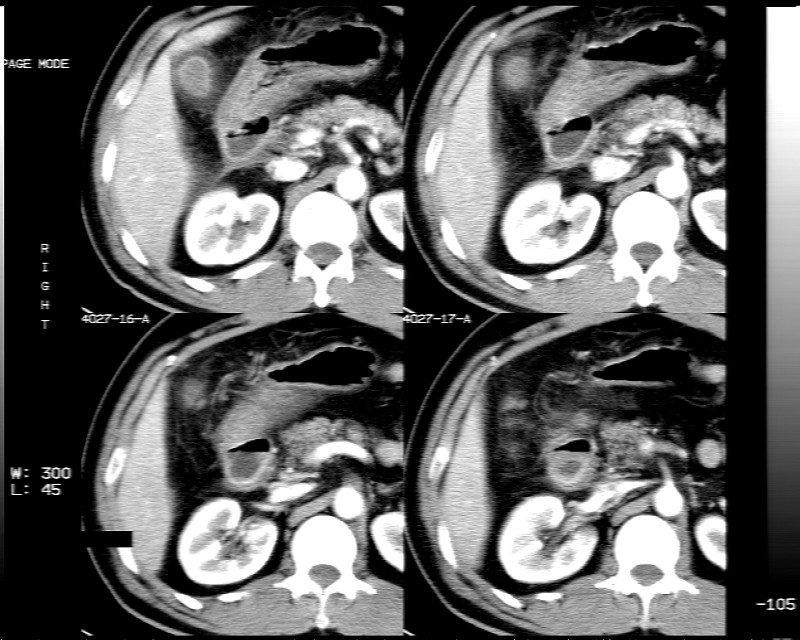

男性,52岁,腹痛,无发热,生化检查无明显异常,既往有胰腺炎病史,经治疗好转出院。

胆囊炎,肝脓肿(周围可见异常灌注)

1)考虑肝左叶内侧段肝脓肿,不排除转移瘤。2)脂肪肝。3)慢性胆囊炎。4)十二指肠降部肿瘤可能。

胆囊炎、脂肪肝、肝脓肿。